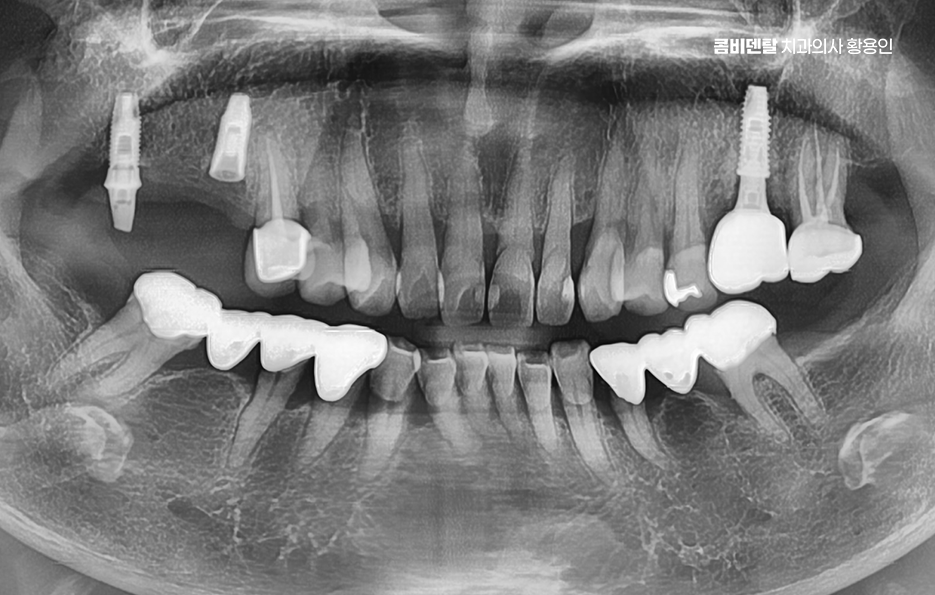

출처 아카이브 열기처음엔 그저 잇몸이 조금 붓는 정도였어요. 양치할 때 피가 나는 것도 자주 있는 일이니까 대수롭지 않게 넘겼어요, 치실을 쓰다가 피가 묻어 나오는 건 오히려 "잘 닦고 있구나" 하고 착각했어요. 그런데 어느 날부터인가 그 붓기가 자주 반복되기 시작했고, 입 안이 자꾸 텁텁하고, 입 냄새도 예전보다 쉽게 났어요, 양치를 아무리 열심히 해도 개운하지 않은 느낌이 계속됐어요. 그러면서 잇몸이 서서히 내려앉기 시작했고, 그 변화가 눈에 보이기 시작한 순간부터는 더 이상 가볍게 넘길 수 없었어요. 예전보다 치아 뿌리 쪽이 더 드러나 보이고, 잇몸선이 들쑥날쑥해지면서 거울을 볼 때마다 마음이 무거워졌어요. 크게 달라진 건 치아 사이가 눈에 띄게 벌어지기 시작했다는 거였어요.

이처럼 나이가 들수록 치아 사이 벌어짐이 잇몸이 약해지면서 더욱 심해지는 경우가 많은데 이러한 문제는 단순히 치아 배열만의 문제가 아니라 치아 수명과도 직결될 수 있는 큰 문제로도 볼 수 있는데요

치아 사이가 벌어지는 현상은 보기에는 단순한 틈처럼 느껴질 수 있지만 그 원인이 치주질환 때문이라면 단순히 공간만 메우는 식의 접근으로는 해결되지 않으며 치주질환이라는 건 치아를 지탱하고 있는 잇몸과 치조골, 그러니까 잇몸 뼈 자체가 서서히 무너져가는 질환이기 때문에, 그 과정에서 심하면 치아가 흔들리고, 치아 사이의 지지가 약해지면서 점점 틈이 벌어지게 되며 이 틈은 시간이 지나면서 점점 더 넓어지고 깊어지는 방향으로 진행될 수 있어요

하지만 치조골이 이미 많이 흡수돼서 치아가 흔들리거나 벌어진 틈이 너무 넓은 경우에는 단순한 잇몸 치료만으로는 회복이 어려워지며 이럴 때는 치주외과적 접근이 필요해지며 대표적으로 치주소파술, 치은박리소파술과 같이 보다 심화된 잇몸 치료가 필요할 수 있어요